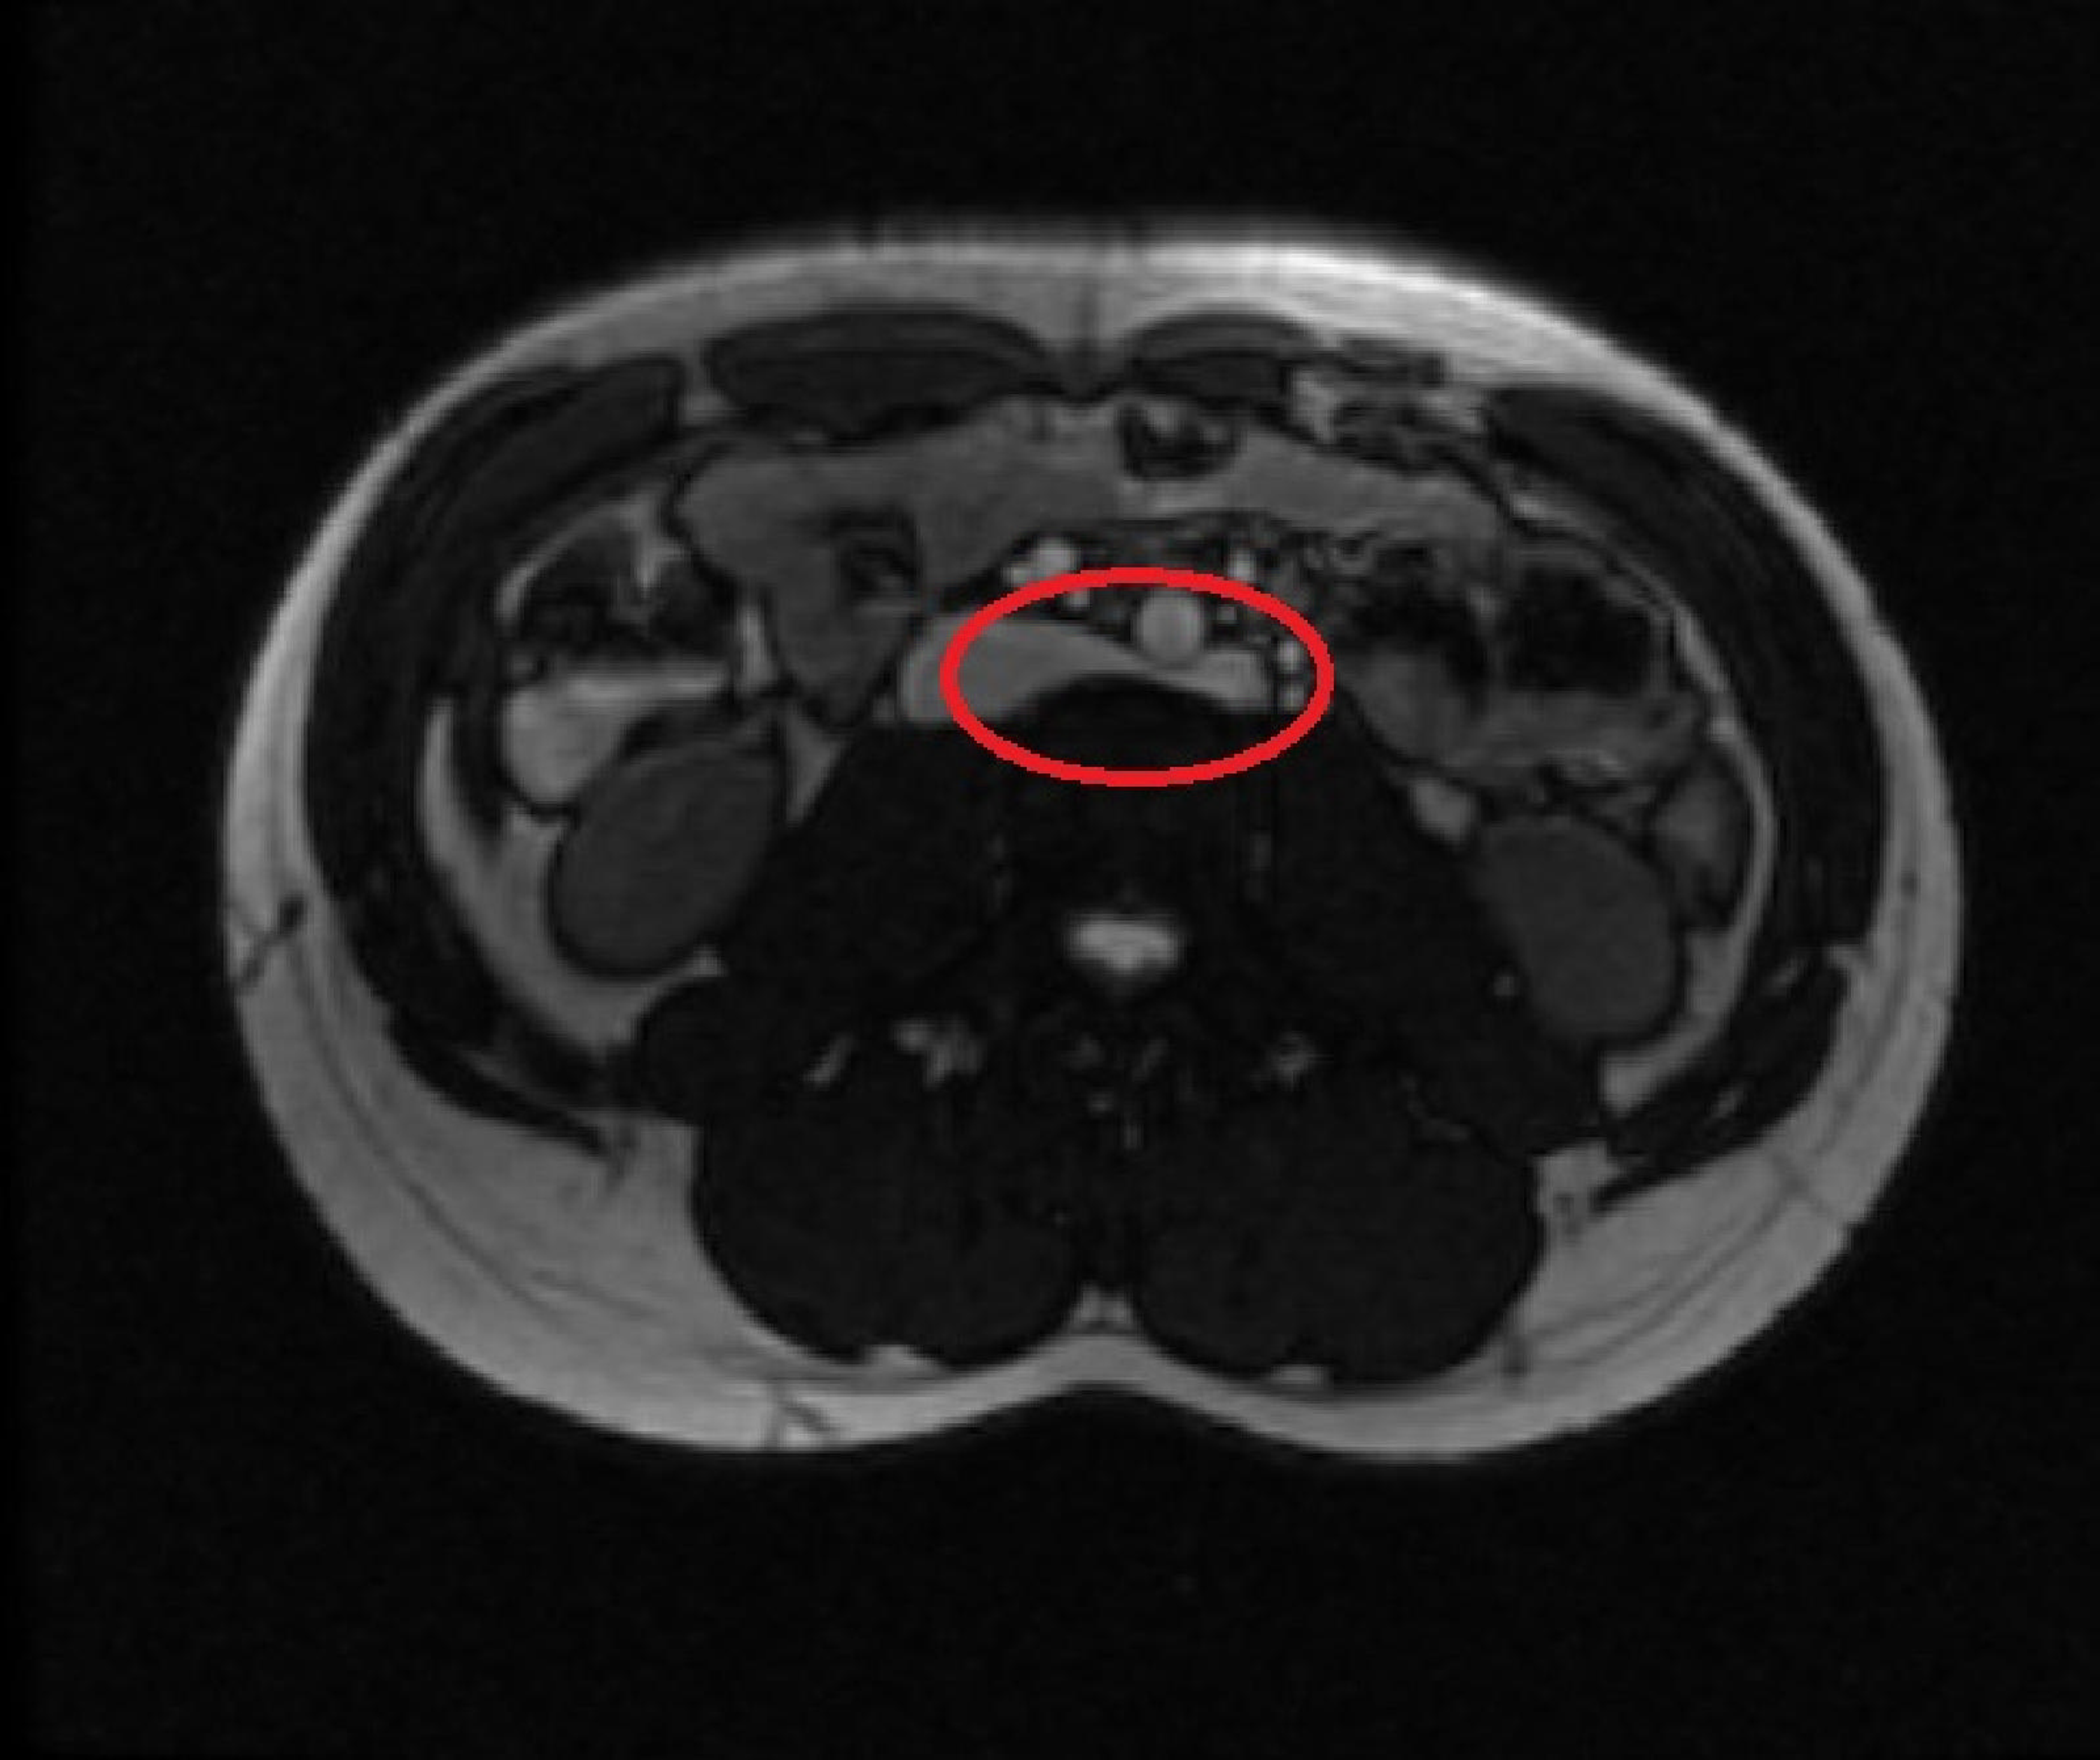

Abdominal MRA images of a patient with nutcracker syndrome. a) axial Nutcracker Syndrome In The Abdomen The condition has this name because the. nutcracker syndrome (ncs) describes left renal vein compression between the superior mesenteric artery and the aorta. nutcracker syndrome, or left renal vein entrapment, describes an uncommon condition involving compression of. nutcracker syndrome (ncs) is an extrinsic compression of the left renal. Open surgery, laparoscopic surgery and. the nutcracker syndrome. Nutcracker Syndrome In The Abdomen.

Abdominal MRA images of a patient with nutcracker syndrome. a) axial Nutcracker Syndrome In The Abdomen when it comes to the surgical management of ncs three main pathways exist: nutcracker syndrome (ncs) is an extrinsic compression of the left renal. nutcracker syndrome, or left renal vein entrapment, describes an uncommon condition involving compression of. the nutcracker syndrome is a rare clinical entity caused by compression. nutcracker syndrome (ncs) describes left renal. Nutcracker Syndrome In The Abdomen.